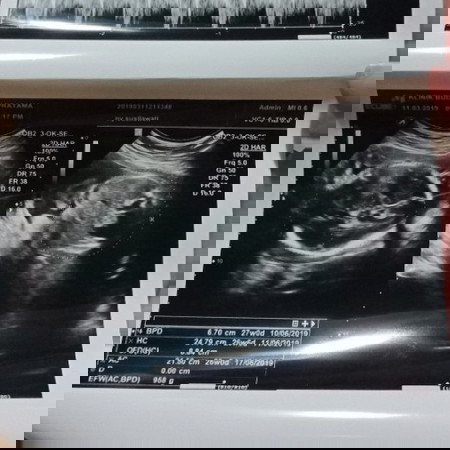

kehamilan sudah menginjak 27 minggu ...tetapi JK nya msh keliatan juga.semalam di Usg ktny posisi kepala udh di bawah udh bagus..tp gender nya lom ketahuan juga krna ngumpet ??